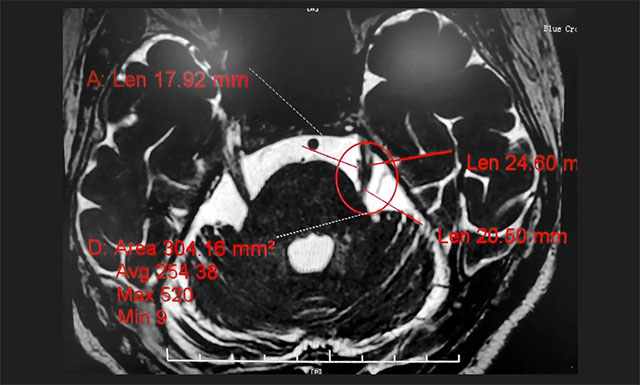

行三叉神经磁共振断层血管成像(MRTA)检查后,提示患者左侧三叉神经与周围小血管关系密切。

▲ MRTA检查提示患者左侧三叉神经与周围小血管关系密切